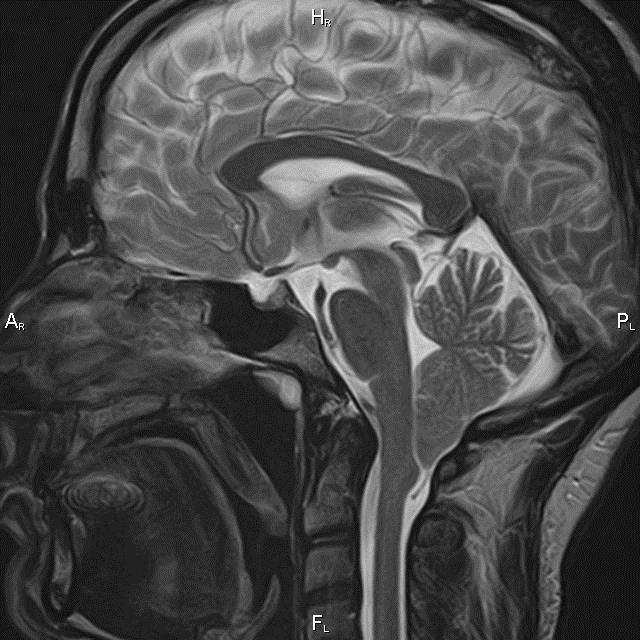

Ataxia cerebelosa aguda en niños, es el repentino movimiento muscular descoordinado debido a una enfermedad o lesión al cerebelo en el cerebro. Síntomas, diagnostico y tratamiento. resonancia magnética, tomografía axial multicorte y estudios especiales.